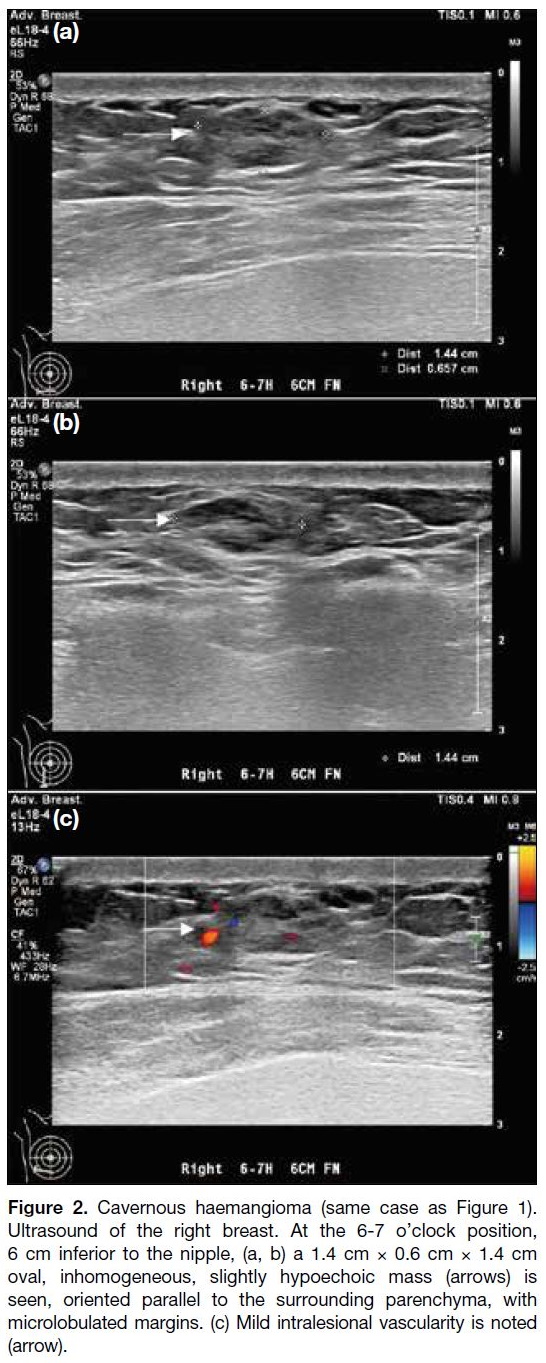

Sonographically, they are similar to their shape on

mammography and are oriented in a parallel manner

(Figures 2 and 3).[2] Their echogenicity is variable,[2] and

they may exhibit non-specific vascular flow.[3] Overall,

there are no definitive imaging features to suggest

benignity or malignancy. Histologically, these lesions

may present as a proliferation of variably sized, ectatic

blood vessels separated by fibrotic stroma.

Figure 2. Cavernous haemangioma (same case as Figure 1). Ultrasound of the right breast. At the 6-7 o’clock position, 6 cm inferior to the nipple, (a, b) a 1.4 cm × 0.6 cm × 1.4 cm oval, inhomogeneous, slightly hypoechoic mass (arrows) is seen, oriented parallel to the surrounding parenchyma, with microlobulated margins. (c) Mild intralesional vascularity is noted (arrow).